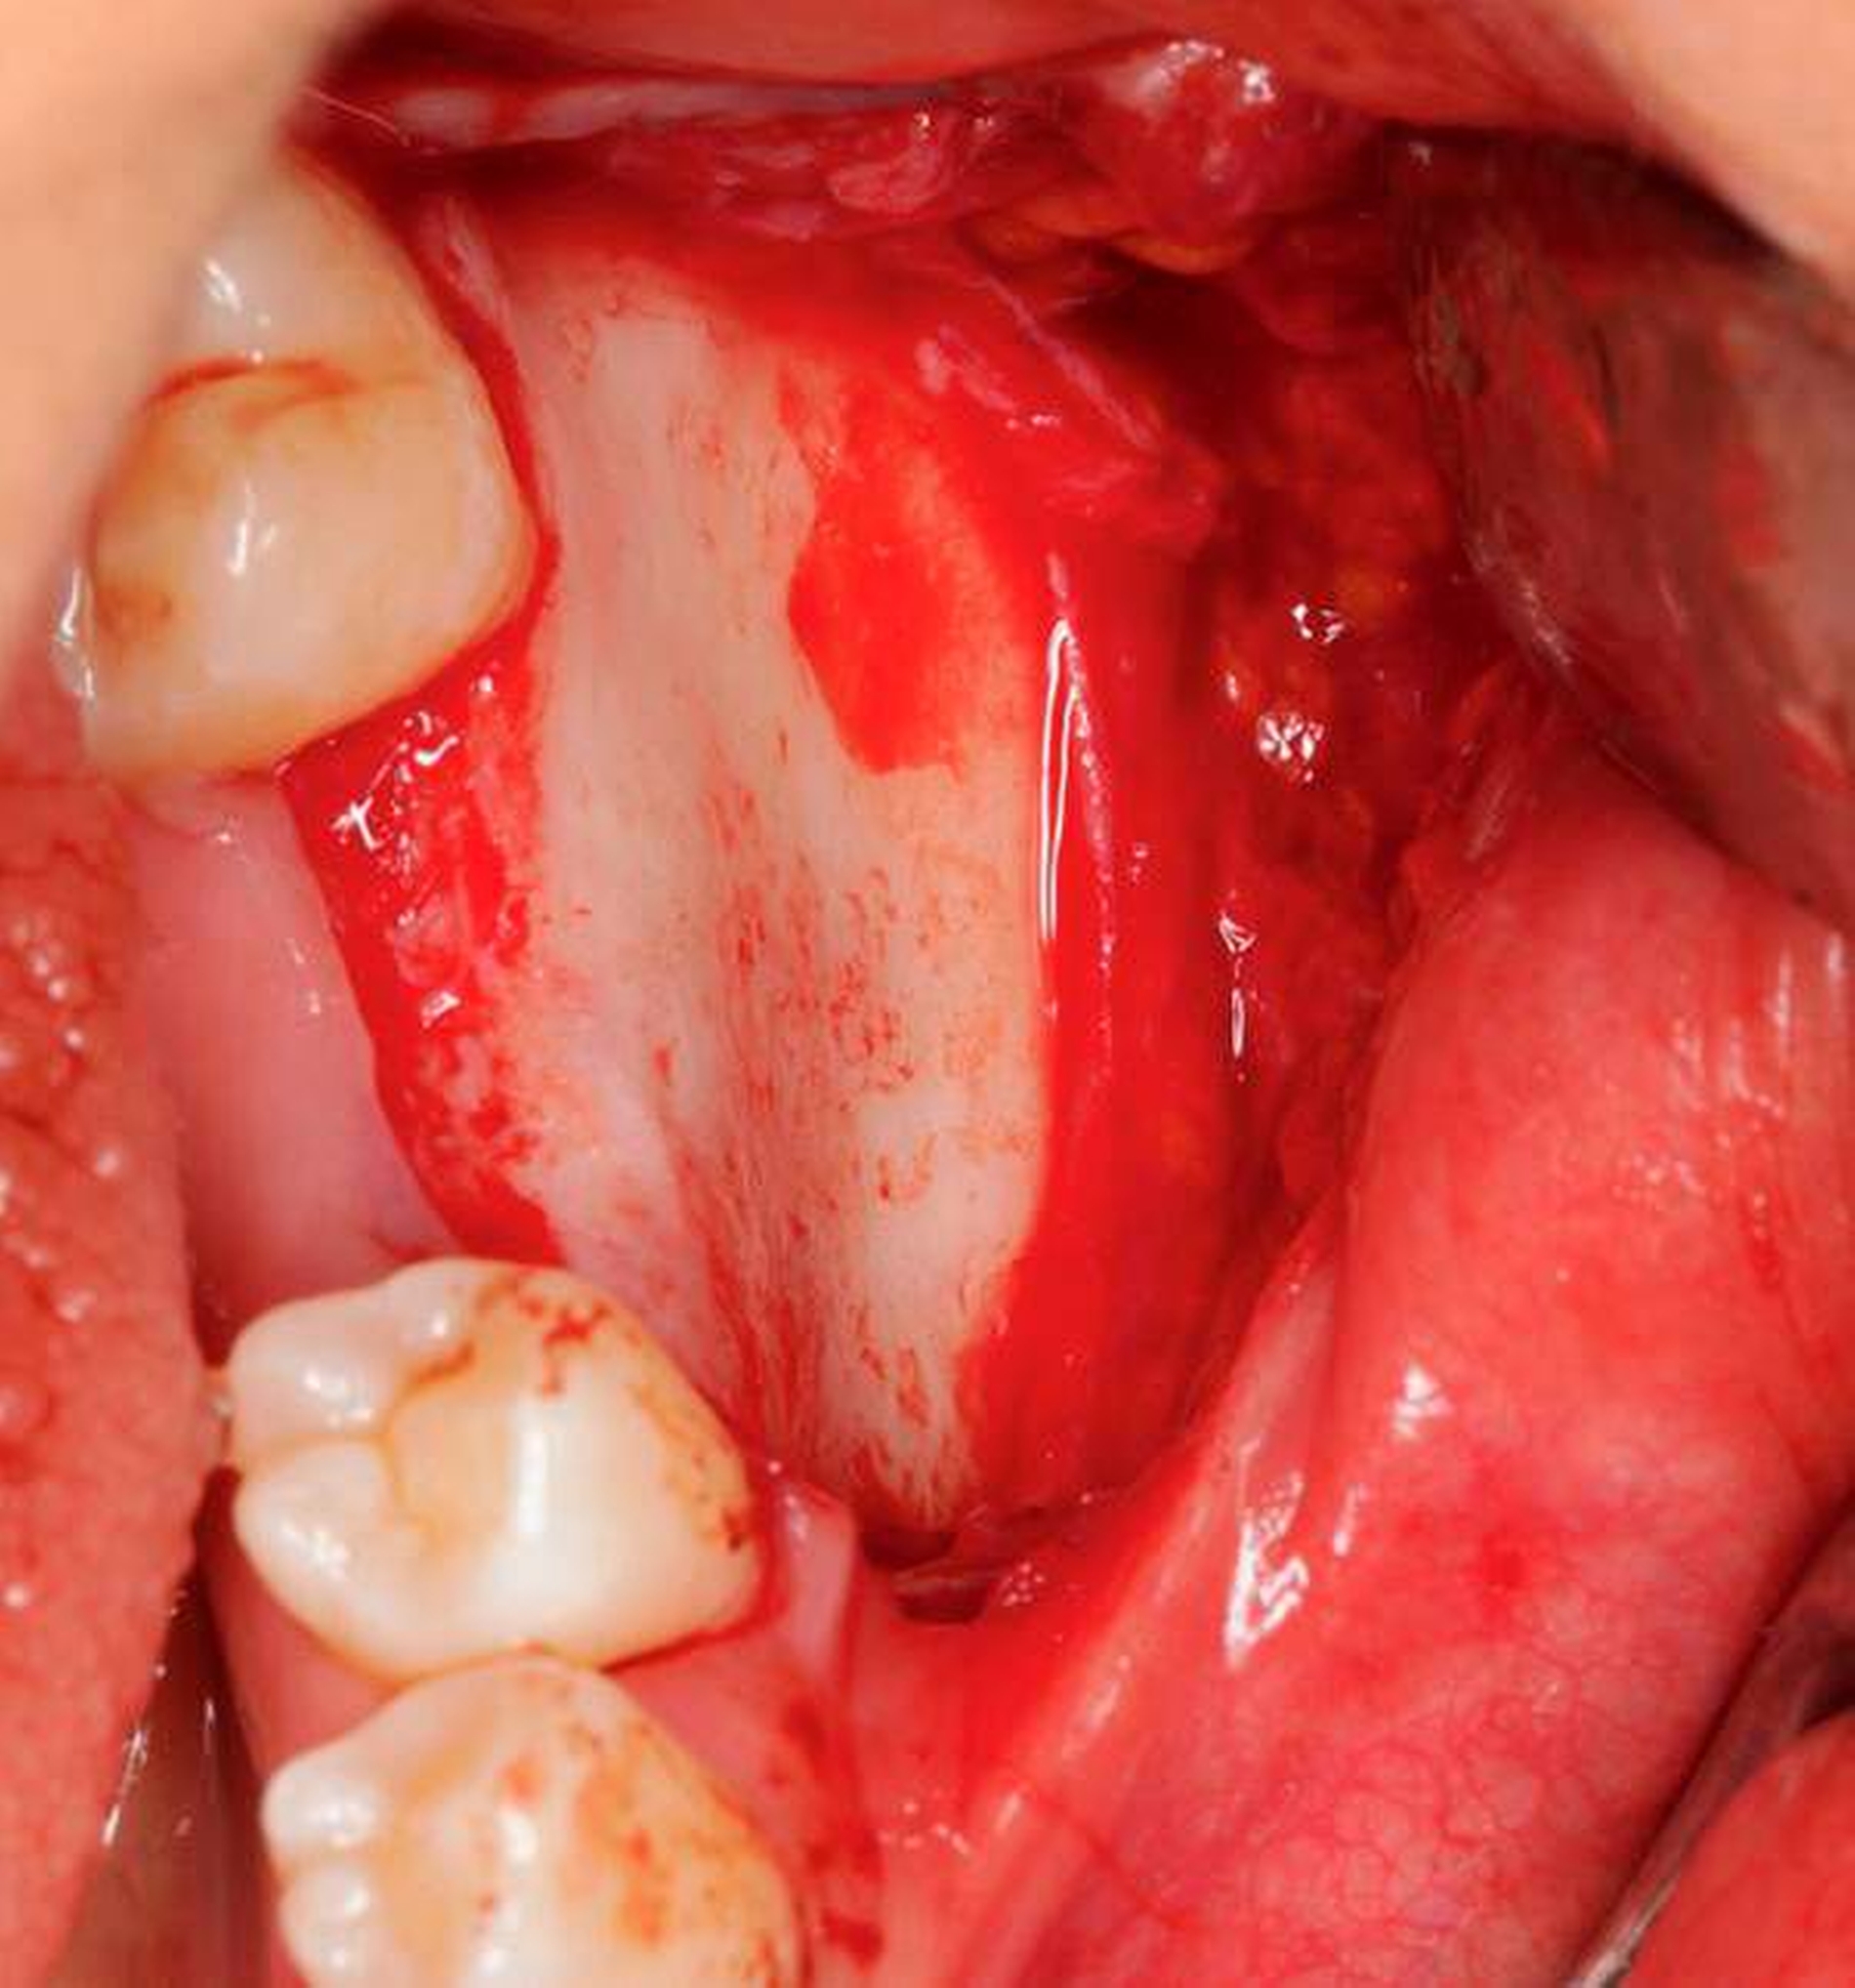

Auch radiologisch ließen sich keine Auffälligkeiten darstellen (Abbildung 1). Aufgrund der lang anhaltenden Persistenz und auf Wunsch der Patientin entschieden wir uns für eine chirurgische Inspektion mit Option auf Entfernung des Tumors. Analog zur Schnittführung der Weisheitszahnentfernung wurde das Gewebe Regio 36 marginal mit einer mesialen und distalen Entlastung eröffnet und ein Spaltlappen gebildet. Bis zur verdächtigen Raumforderung wurde stumpf mit der Schere präpariert (Abbildung 2), wobei sich die Läsion schließlich als abgekapselte Struktur darstellte, die sich sehr gut aus dem umliegenden Gewebe entfernen ließ. Das klinische Erscheinungsbild der Raumforderung entsprach am ehesten der eines Lipoms (Abbildung 3). Nach kompletter Entfernung der Raumforderung (Abbildung 4) wurde die Wunde mit Nähten speicheldicht verschlossen (Abbildung 5).

Die histopathologische Untersuchung ergab eine abszedierende, floride Entzündung aus zahlreichen Histiozyten und massenhaft neutrophilen Granulozyten sowie eine große Aktinomyces-Druse im Zentrum der Läsion. Der chirurgischen Therapie schloss sich eine über zwei Monate erstreckende Therapie mit Amoxicillin und Clavulansäure an.